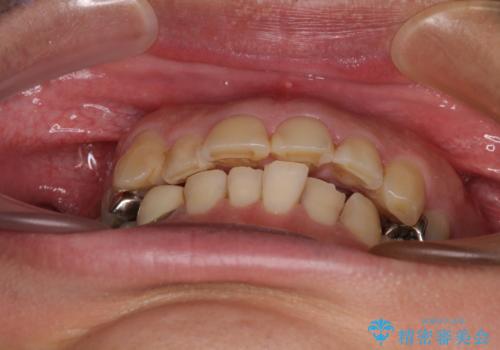

- 近医にて下顎奥歯の抜歯が必要と言われたとのことで来院された患者様です。

診察の結果、奥歯は左右ともに抜歯が必要な状態でした。

他の銀歯も気になっており、セラミックにしたいとの要望があり、詳しくお話をすると、デコボコの歯ならびも整えたいとのことでした。

抜歯が必要な歯は事前に抜歯をし、その後ワイヤー装置にて歯列矯正を行い、途中でインプラントを埋入し、オールセラミッククラウンにて補綴治療を行うこととしました。